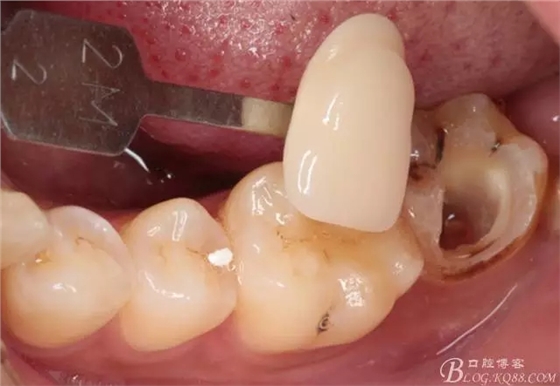

第四次復(fù)診,37叩(—)。此次行冠部修復(fù),因涉及38的拔除,患者不愿拔除,與患者介紹修復(fù)材料與方法,擬37E.max嵌體修復(fù),術(shù)前常規(guī)簽修復(fù)知情同意書。

去除暫封物,拍照,比色。

流動樹脂充填窩洞,金霸王車針和鎢鋼車針常規(guī)備牙,配合硅膠尖拋光,頰側(cè)排00排齦線。硅橡膠二次法取模,記錄咬頜關(guān)系,臨時樹脂充填窩洞。